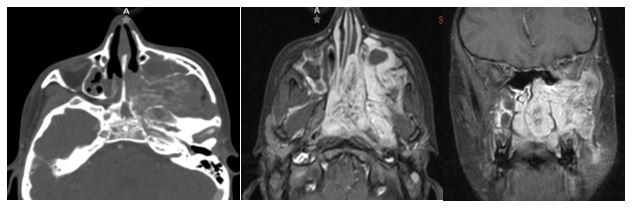

3. 10/2017. Masculino 17 años con obstrucción nasal de inicio gradual, epistaxis recurrente derecha, masa la cavidad nasal bilateral y abombamiento de paladar blando de 4 años de evolución. TC y RM con extensión a naso y orofaringe con extensión a seno maxilar, fosa pterigomaxilar, infratemporal derecha y extensión intracraneal mínima. Clasificación IIIA (Radkowski) IV (Chandler). Se realiza angiografía, embolización de ramas de carótida externa bilateral, y resección vía endoscópica, transpalatina y Degloving, resección de 95% de tumor con tumor residual en fosa infratemporal, posterior radioterapia, con reducción gradual de tumor en los últimos 8 meses.

3

4. 03/2018. Masculino 16 años con obstrucción nasal de inicio gradual, epistaxis recurrente izquierda, masa la cavidad nasal bilateral y abombamiento de paladar blando de 3 años de evolución. TC y RM con extensión a seno maxilar izquierdo fosa infratemporal, fisura infraorbitaria e intracraneal izquierdo. Clasificación IIIA (Radkowski) IV (Chandler). Se realiza angiografía, embolización y resección vía Degloving, con resección completa de tumor, buena evolución posquirúrgica a 6 meses, sin recurrencia.

4